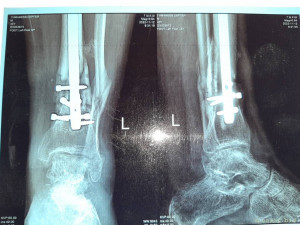

Вот что со мной произошло: летом прошлого 2022 года я неудачно упал, и сломал левую ногу, да так, что всё не закончлось просто гипсом. Перелом был сложным, пришлось делать операцию, ставить биос. Операция прошла с осложнениями, был свищ, нога после операции долго не заживала. Потом сломался крепёжный саморез, стало ещё хуже. Заболела правая нога в колене и бёдре. На приёме у врача сказали нужна операция! И в ближайшее время! Но я на больничном уже целый год, и после такого продолжительного лечения, все мои финансы на нуле. Ходить не могу, спать не могу, мучают постоянные боли. У меня развился сахарный диабет, ноги болят, появилась венозная недостаточность и варикоз. Мне всего 41 год. Получается я останусь инвалидом навсегда... Но у меня есть двое детей 5 и 14 лет... В данный момент я не могу встать на ноги из-за отсутствия финансовых средств. Моя мама Лариса Андреевна, помогает мне по мере своих сил. Ей приходится работать на производстве. Но ей уже 75 лет...

Нужна помощь сыну сотрудницы Не может ходить. - 20230719_135457.jpg